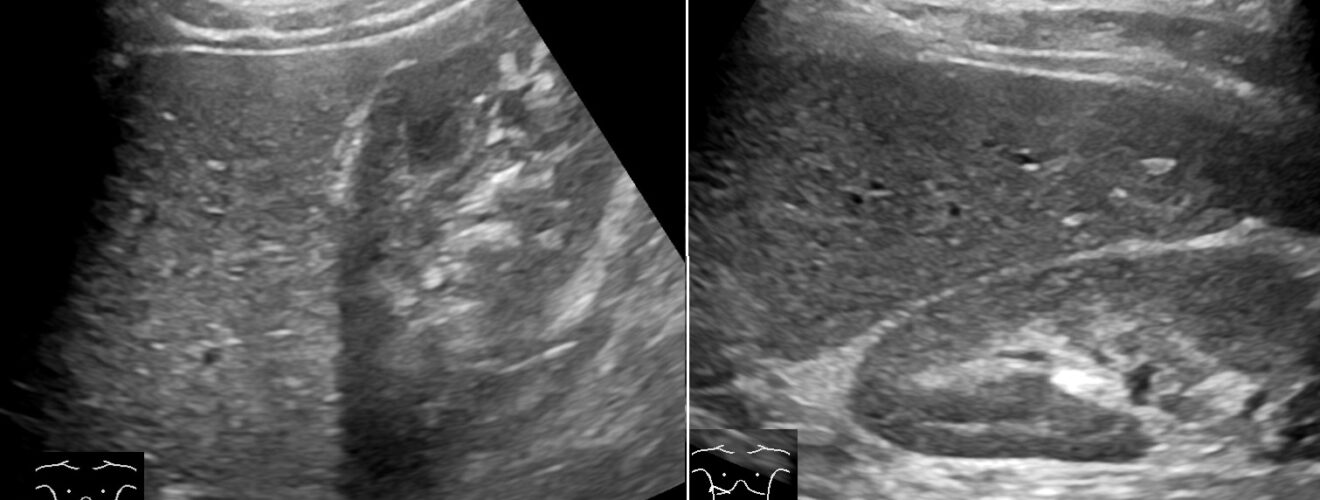

Abdominal ultrasonography of the liver and right kidney. Wikimedia

腹部エコーのデモンストレーション

- プローブをどう当てるとどういう画像になるか、解剖体もみながら理解していこう

- 肝臓と肝静脈と門脈、胆嚢、肝臓と右腎とモリソン窩、脾静脈と膵臓、脾臓と左腎、膀胱

- 胎児、胎児の心臓・脊柱・肋骨など、胎盤、臍帯と臍帯の血管